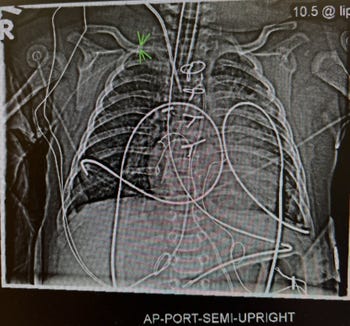

Given the proximity of the axillary artery to the cerebral circulation, adopting cautious flushing techniques becomes integral to patient safety (Figure). Extrapolating from these studies to the flushing of axillary arterial lines suggests the following as reasonable precautions pending studies to the contrary: (1) flush volumes should be minimized, ideally as low as 1 mL when possible. However, unless the flush volume is administered via a stopcock very close to the arterial cannula, we acknowledge that larger volumes may be required for adequate line maintenance; (2) the velocity of the flush should not exceed 1 mL/s and more ideally, should be 0.5 mL/s. This speed, in practice, feels profoundly slow, but is likely the most important factor to reduce embolization; and (3) maintain a vertical orientation of the syringe (with the plunger at the top) to further reduce embolization risk. We feel that this simple aspect of our care is worth highlighting, especially to our trainees and rotators who may have limited pediatric exposure (as well as clinicians in the ICU). By emphasizing these best practices, we can enhance their awareness and competency, ultimately improving outcomes for our young patients. As this field continues to evolve, staying informed and vigilant about these procedures will remain a cornerstone of effective pediatric anesthetic care.

Figure Legend: CXR in an infant with a right axillary arterial catheter size 24G and length 5 cm. Green arrows indicate tip of the catheter very close to the subclavian artery.